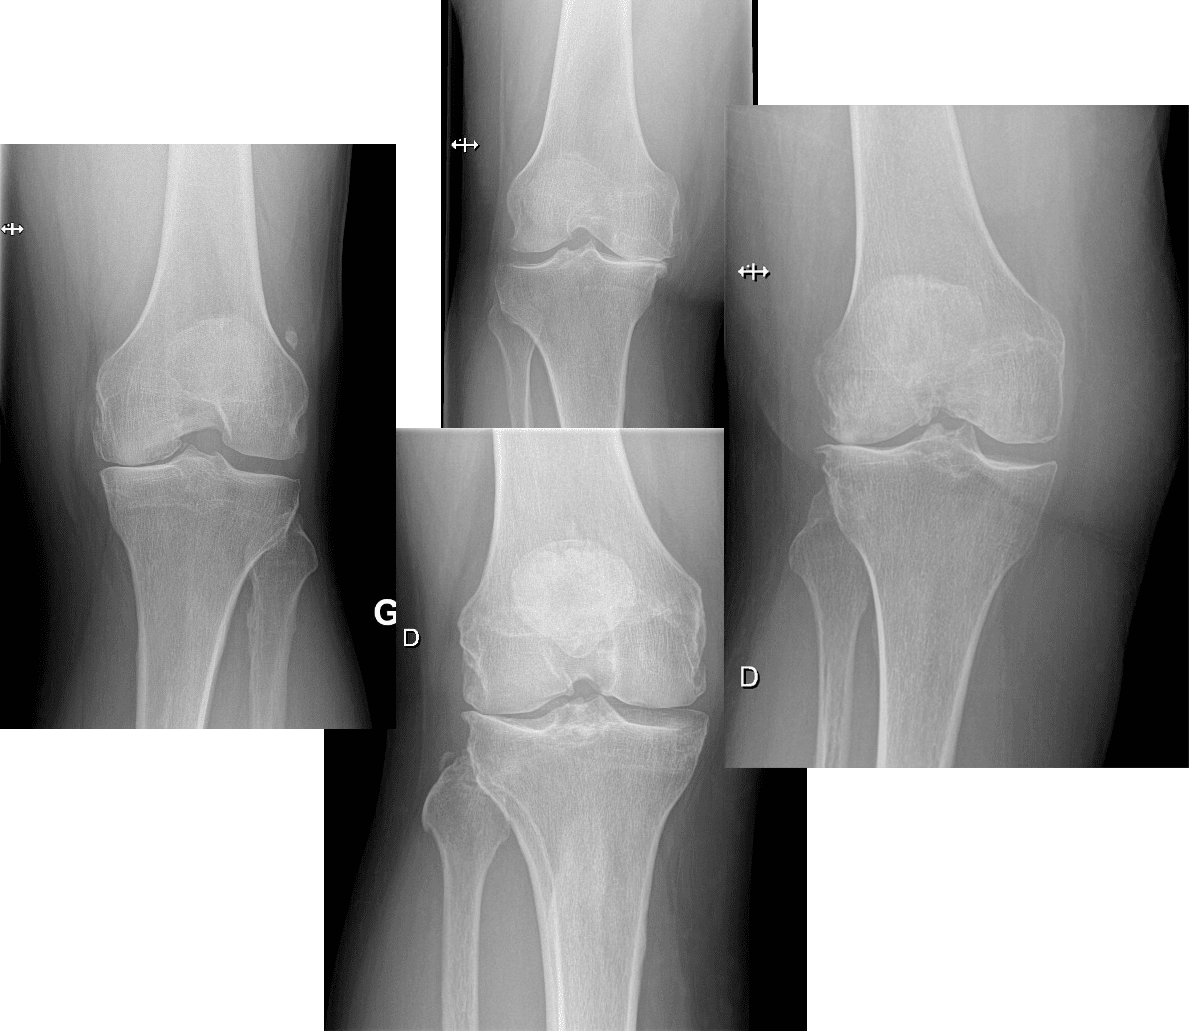

La confirmation du diagnostic peut être simple, parfois avec la réalisation d’une simple radiographie.

Des examens complémentaires sont rarement nécessaires . Elle sert à exclure les lésions associées ou à èvaluer le niveau d’usure. Le chirurgien pourrait vous demander une échographie, un arthro-scanner ou une résonance magnétique.

L’usure de ce cartilage avec l’amincissement de son épaisseur représente l’arthrose.

Quand ce cartilage est usé …c’est l’arthrose.

Normalement le cartilage est nourri par le liquide de l’articulation qui « lave » cette surface cartilagineuse à chaque mouvement. Avec l’usure, le cartilage de l’articulation devient moins élastique et il s’assèche. Des fissures apparaissent et le cartilage devient irrégulier. L’os n’est plus couvert par le cartilage, est mis à nu et à la fin les surfaces osseuses sont en contact direct. Ceci déclenche des douleurs violentes. Le genou se déforme (position en forme de X ou de O).